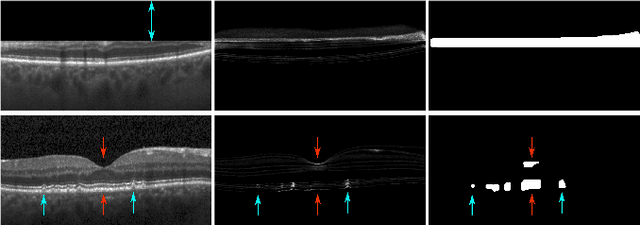

Abstract:Diagnosis and treatment guidance are aided by detecting relevant biomarkers in medical images. Although supervised deep learning can perform accurate segmentation of pathological areas, it is limited by requiring a-priori definitions of these regions, large-scale annotations, and a representative patient cohort in the training set. In contrast, anomaly detection is not limited to specific definitions of pathologies and allows for training on healthy samples without annotation. Anomalous regions can then serve as candidates for biomarker discovery. Knowledge about normal anatomical structure brings implicit information for detecting anomalies. We propose to take advantage of this property using bayesian deep learning, based on the assumption that epistemic uncertainties will correlate with anatomical deviations from a normal training set. A Bayesian U-Net is trained on a well-defined healthy environment using weak labels of healthy anatomy produced by existing methods. At test time, we capture epistemic uncertainty estimates of our model using Monte Carlo dropout. A novel post-processing technique is then applied to exploit these estimates and transfer their layered appearance to smooth blob-shaped segmentations of the anomalies. We experimentally validated this approach in retinal optical coherence tomography (OCT) images, using weak labels of retinal layers. Our method achieved a Dice index of 0.789 in an independent anomaly test set of age-related macular degeneration (AMD) cases. The resulting segmentations allowed very high accuracy for separating healthy and diseased cases with late wet AMD, dry geographic atrophy (GA), diabetic macular edema (DME) and retinal vein occlusion (RVO). Finally, we qualitatively observed that our approach can also detect other deviations in normal scans such as cut edge artifacts.

Abstract:In this paper, we introduce a Bayesian deep learning based model for segmenting the photoreceptor layer in pathological OCT scans. Our architecture provides accurate segmentations of the photoreceptor layer and produces pixel-wise epistemic uncertainty maps that highlight potential areas of pathologies or segmentation errors. We empirically evaluated this approach in two sets of pathological OCT scans of patients with age-related macular degeneration, retinal vein oclussion and diabetic macular edema, improving the performance of the baseline U-Net both in terms of the Dice index and the area under the precision/recall curve. We also observed that the uncertainty estimates were inversely correlated with the model performance, underlying its utility for highlighting areas where manual inspection/correction might be needed.